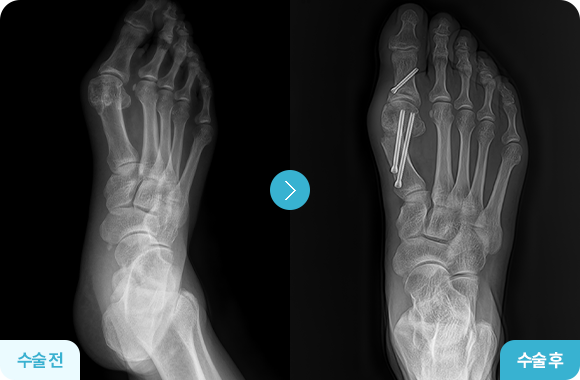

무지외반교정술 전후사진

교정된 뼈를 생체적합성 핀으로 고정 후

봉합하며, 조기 보행이 가능합니다.